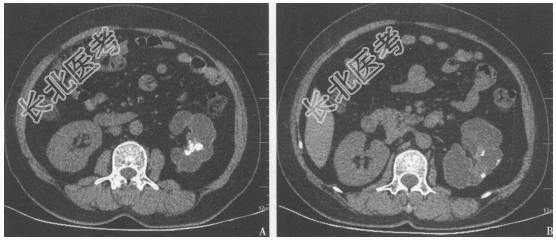

- [材料题] 患者男性,28岁,因尿频,尿急,左侧睾丸疼痛3个月就诊。当地医院诊断为慢性前列腺炎,口服左氧氟沙星1个月,症状略好转。现因病情反复来诊。查体:左侧附睾可触及黄豆大小包块。尿常规:白细胞15个/HP,红细胞10个/HP。前列腺液常规:卵磷脂小体50%,白细胞15个/HP。

- 简答题2、患者完善了CT检查(图38)。该患者可能的诊断是